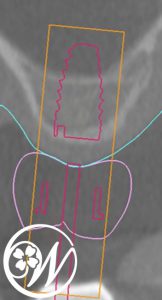

術前にはCTデータを用いたシミュレーションを行い、サージカルガイドを使用して埋入位置・角度・深さを正確に設計。

インプラント埋入前シュミレーション サージカルガイド